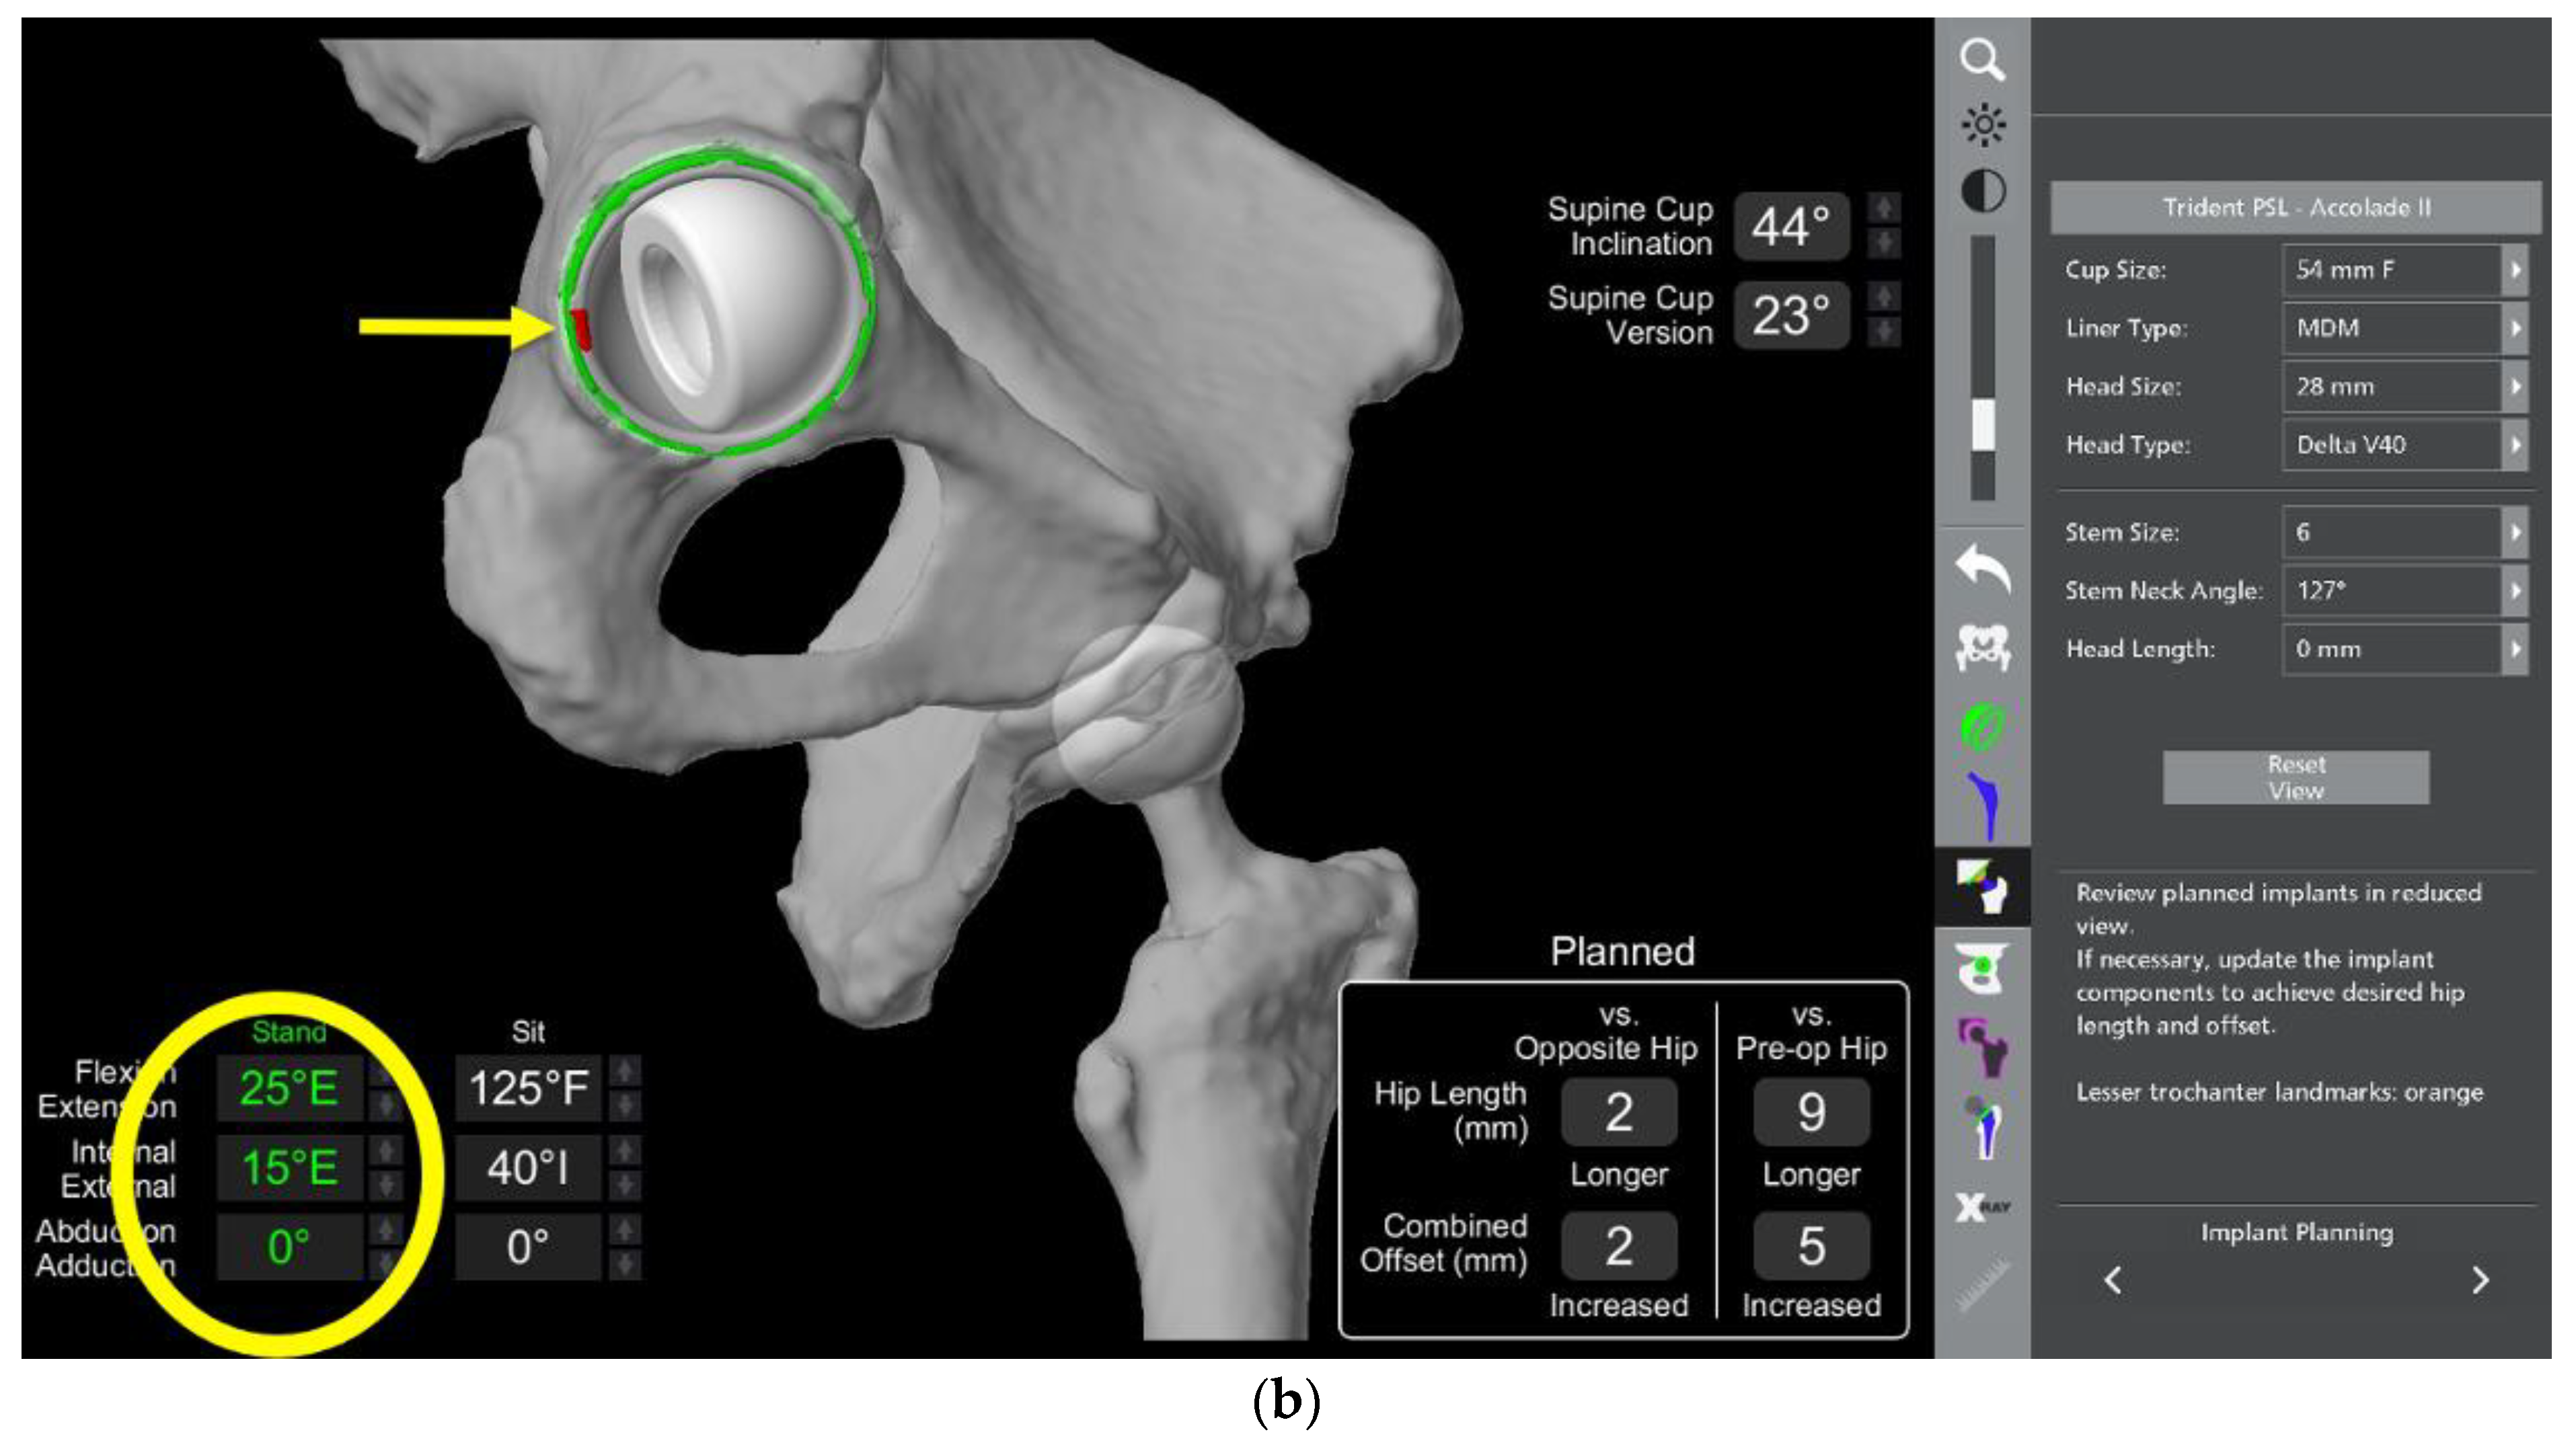

- In this case, the native femoral retroversion (−6 degrees) posed a challenge in avoiding impingement (Figure 7). Upon assessing VROM, bone-on-bone and implant-on-implant impingement in deep flexion were noted (Figure 8). Using the robotic software, the planned femoral version was corrected to +16 in the femoral broach (Figure 9a,b).

- VROM was performed again, and impingement in flexion was eliminated (Figure 10). In extension, upon subtracting the femur, it became apparent that there was a small area of impingement secondary to an anterior osteophyte which was planned to be removed after cup insertion during the operation (Figure 11a,b).